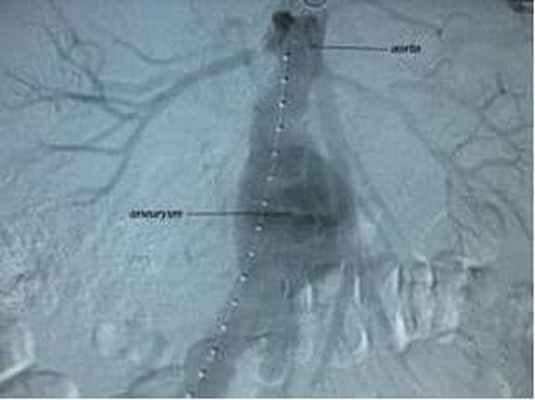

- Рентгенконтрастная ангиография;

Лечение аневризмы брюшной аорты

Выбор лечения аневризмы зависит от наличия симптомов и размера аневризмы. Экстренная операция необходима при разрыве аневризмы. Такие операции сопровождаются гораздо большим риском для пациента, чем при плановых операциях, когда есть возможность полностью обследовать пациента и тщательно подготовить к хирургическому вмешательству.

При атеросклерозе поражается не только аорта, но и другие артерии, в частности артерии сердца (коронарные артерии) и сонные артерии, кровоснабжающие головной мозг. Поэтому прежде чем выполнять операцию по поводу аневризмы аорты в центре сердечно-сосудистой хирургии имени А.Н.Бакулева производится тщательное обследование всех сосудистых бассейнов, чтобы свести риск операции к минимуму. Операция заключается в замещении пораженного участка аорты искусственным сосудистым протезом.